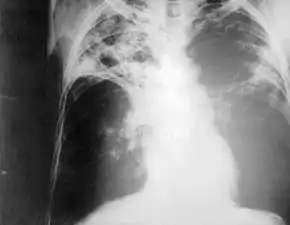

![]() Chest radiography showing advanced bilateral pulmonary tuberculosis. Source: CDC | |

Chest photofluorography, or abreugraphy (also called mass miniature radiography), is a photofluorography technique for mass screening for tuberculosis using a miniature (50 to 100 mm) photograph of the screen of an X-ray fluoroscopy of the thorax, first developed in 1936.